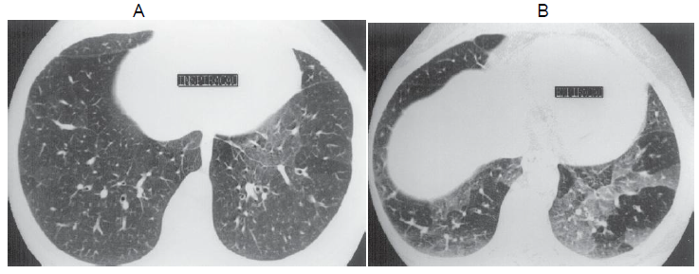

Analise as imagens abaixo, de uma mesma paciente, e asinale a opção com a patologia que melhor as representam

a) Imagem em inspiração revela discreta atenuação em mosaico. B) Imagem em expiração mostra melhor as anormalidades.